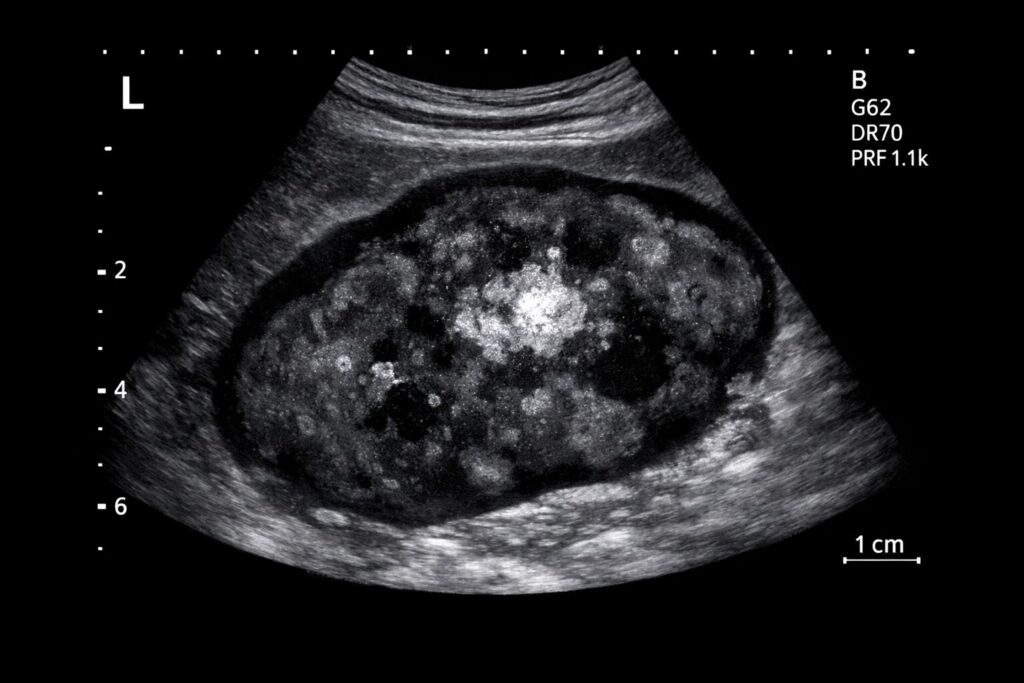

• レントゲン・CT(骨破壊・転移評価)

• 骨髄穿刺による細胞診/病理